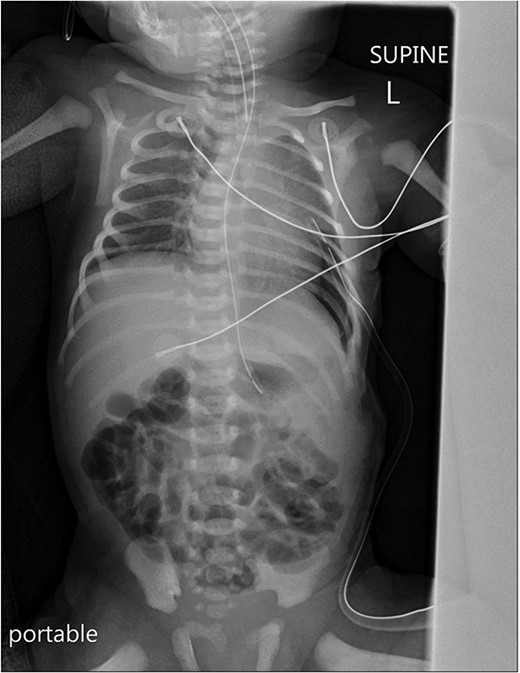

Postoperatively, a chest X-ray revealed a small left-sided pneumothorax that resolved in a few days (Fig. 2). Three days after the surgery, the fentanyl infusion was stopped, and the patient was extubated to a high-flow nasal cannula for 5 days. On the same day, the patient was noted to have a greenish-yellow aspirate. The patient was febrile the day after, a septic screen was done, and the patient was treated with ceftriaxone and vancomycin for 2 weeks. Furthermore, the surgical site was noted to have purulent discharge, for which fusidic acid was locally applied for 2 weeks. Abdominal ultrasound conducted a week after surgery showed an oval collection of fluid with intrinsic echoes, possibly a splenic hematoma, in the left upper quadrant, which was self-limited after 2 months of follow-up (Fig. 3). Before discharge, the patient’s parents were advised on a nursing plan, oral sucrose for analgesia and ranitidine.

A portable X-ray photo of the chest, abdomen and pelvis taken postoperatively shows the expansion of both lungs and midline mediastinal position. A small subpulmonic pneumothorax on the left side is visible, for which a chest tube was inserted.